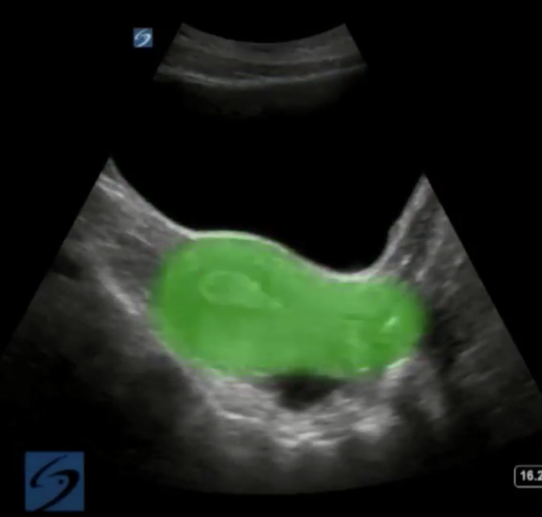

盆腔子宫高亮图像

高亮区域:子宫